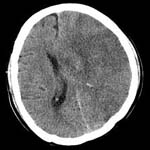

<°íÇ÷¾Ð¼º

³úÃâÇ÷>

<¼ö¼ú

Àü> <¼ö¼ú

ÈÄ>

¿ìÃø

Çǰ¢ºÎ ÃâÇ÷ȯÀÚÀÇ ³úCT¼Ò°ß(¼ö¼úÈÄ Ç÷Á¾ÀÌ

Á¦°ÅµÇ¾îÀÖ´Ù)